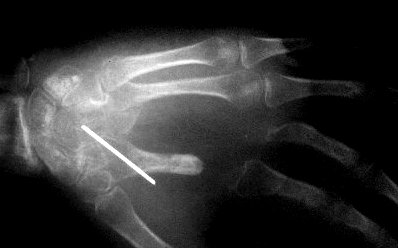

After debridement, no remaining debris. An external fixator was used for temporary stabilization.